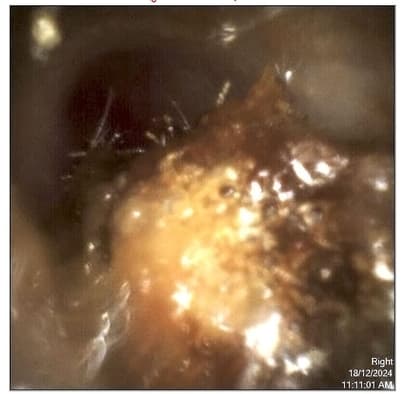

- Examine your ear using a specialised microscope or video otoscope

- Show you the removed wax (if you want to see it!)

- Re-examine your ear to ensure all blockages are cleared